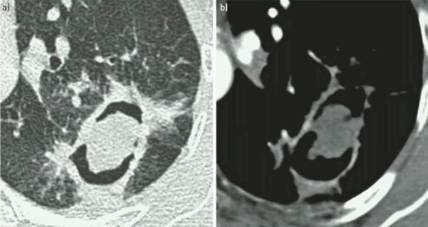

慢性空洞性肺曲霉病(CCPA):最常见,单发或多发的肺空洞(薄壁或厚壁),空洞内可包含一个或多个曲菌球或不规则的腔内物质,具有曲霉菌血清学和微生物学依据,并有明显肺部和全身症状,至少3个多月的观察有放射影像学进展(新发空洞,空洞外周浸润增加及纤维增生增加)。

慢性纤维化性肺曲霉病(CFPA):常因未经规范治疗的CCPA发展而来,至少有两个肺叶的严重纤维化破坏,伴肺功能丧失。而单发空洞伴一个肺叶的严重纤维化性破坏,简称为CCPA影响的肺叶。

亚急性侵袭性肺曲霉病(SAIA):轻度免疫缺陷的侵袭性肺曲霉病患者,发生在1-3个月内,具有可变的影像学特征,包括空洞、结节、有“脓肿形成的进展性实变”。最重要的特征为肺组织发现菌丝,另血液或呼吸液GM试验呈强阳性。